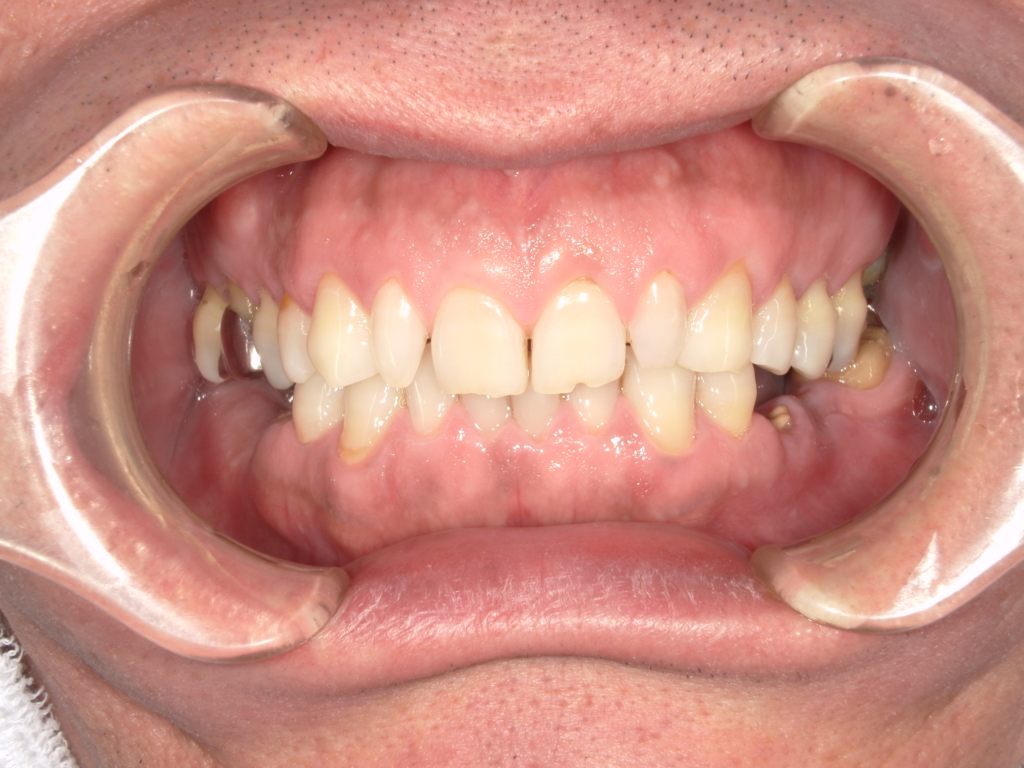

Y様インプラント実例 #44

左の上下の奥歯をインプラントで治療しています。

左下の奥歯は歯を抜くのと同時にインプラントの埋め込みを行っています。

被せものは上下、セラミックスで作っています。

治療前

治療後